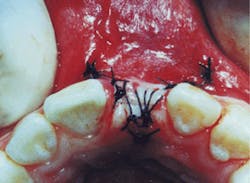

A simple suture is secured with minimal tension over the grafted socket to avoid loss of the OsteoGraf/LD-300 and the Gelfoam (Figure 3). Standard postoperative instructions are given to the patient, and an appointment is scheduled for suture removal in 10 days.

Figure 3